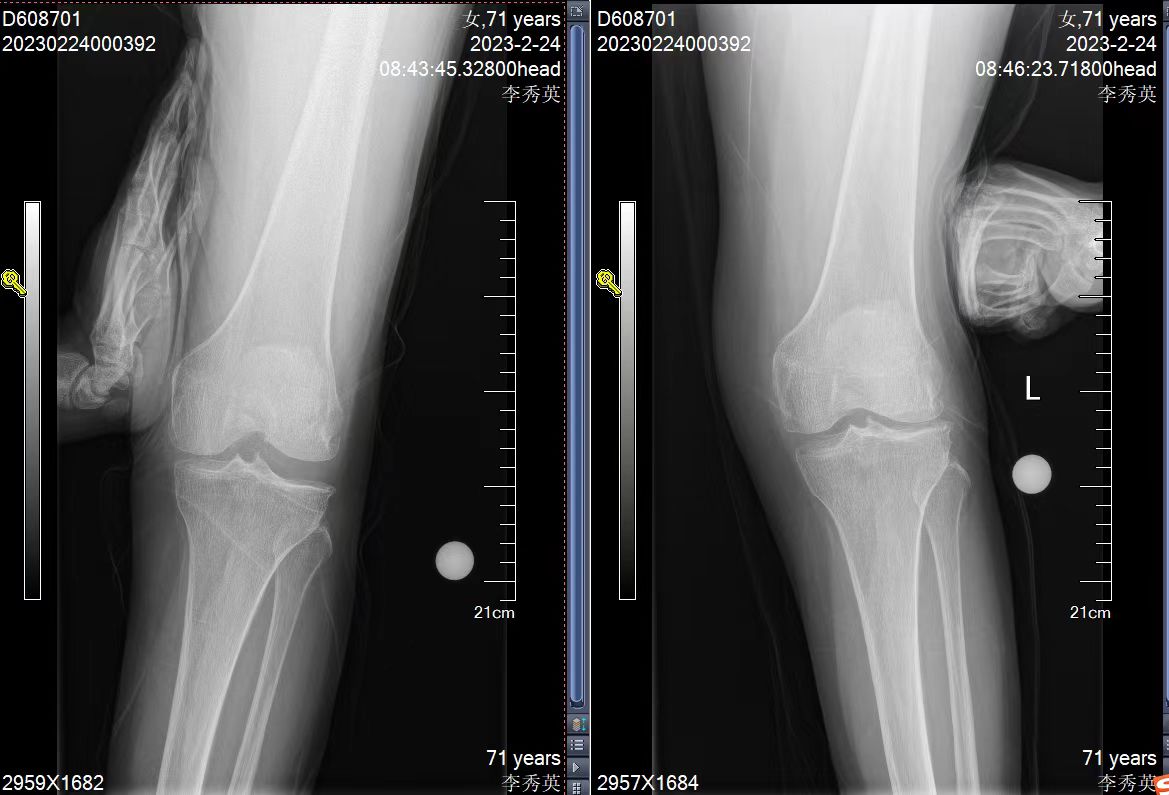

得知西安交通大学第二附属医院王伟教授在洛阳中心医院骨科长期驻科工作后,她抱着试一试的心态来到洛阳市中心医院骨科。王伟教授分析了她的病情:左膝外侧半月板磨损坏了,膝关节外翻变形,而关节其他部分还功能良好,完全可以采用微创保膝手术,保留自己膝关节的大部分。骨科团队给她量身订制了手术方案:外侧单髁关节置换术。家属也联系了北京著名医院的大专家,完全认可手术方案。王伟教授用国际先进的专业术前规划软件,提前进行术前设计,精准预判关节假体大小和安装位置,最终手术仅需7厘米的切口,单髁置换,保膝治疗,取得了康复复周期短,功能恢复好的效果。术后洛阳中心医院骨科王伟民主任、郭哲医师经过数月的耐心随访,解决患者康复中的问题,患者完全恢复了正常生活。精准医疗,量身定制,不仅为患者解决了病痛,而且不必千里迢迢,辗转北京求医。